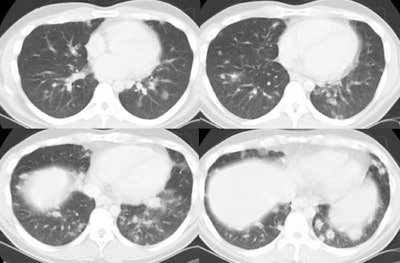

The patient below presented with complaints of cough, malaise, and a low-grade fever. The chest radiograph revealed some patchy left lower lobe airspace disease and vague nodular shadows- particularly in the lower lung zones. A chest CT was performed and demonstrated multiple nodular airspace abnormalities with variable margins. The lesions did not improve despite antibiotic therapy and all cultures were negative. Click images to enlarge. |

Open lung biopsy confirmed the diagnosis of BOOP. Following institution of therapy with steroids the lung lesions resolved. Click images to enlarge.